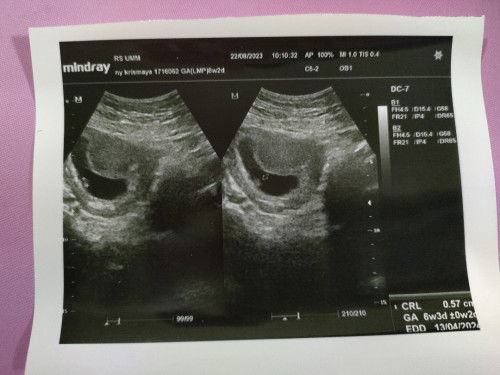

Hasil usg 8w janin berkembang tdk sesuai usia.

Sy awal usg waktu ketahuan hamil 6w, hasil usg nya saat itu hanya kantung blm ada janin, kemudian diminta kembali 2mg lagi. Jdi saat masuk 8w saya kembali melakukan usg. Kemudian dokter mengatakan "janinnya kok masih sangat kecil perkembangannya tdk sesuai dgn usia" dan tdk di lihatkan djj nya lalu sy diminta untuk kembali 2mg lagi. Apa normal ya bund dgn usia hpht 8w tapi hasil usg masih 6w?